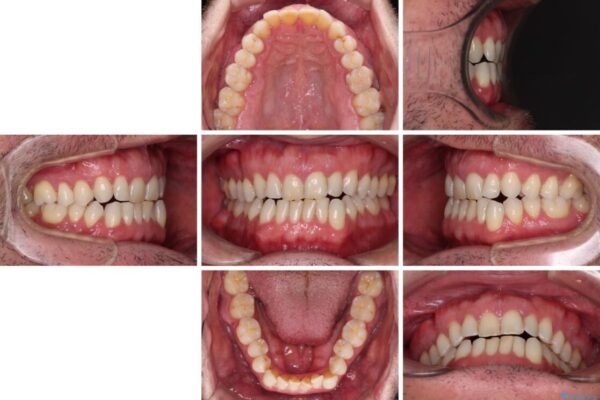

前歯でものを噛みきりたい 目立たない装置でのワイヤー矯正

前歯でものを噛みきりたいとのことで来院された患者様です。

以前矯正治療を経験されたそうですが、舌の突出癖により上下前歯に隙間ができている様子でした。

治療前

• 前歯でものを噛みきりたい 目立たない装置でのワイヤー矯正 治療前画像